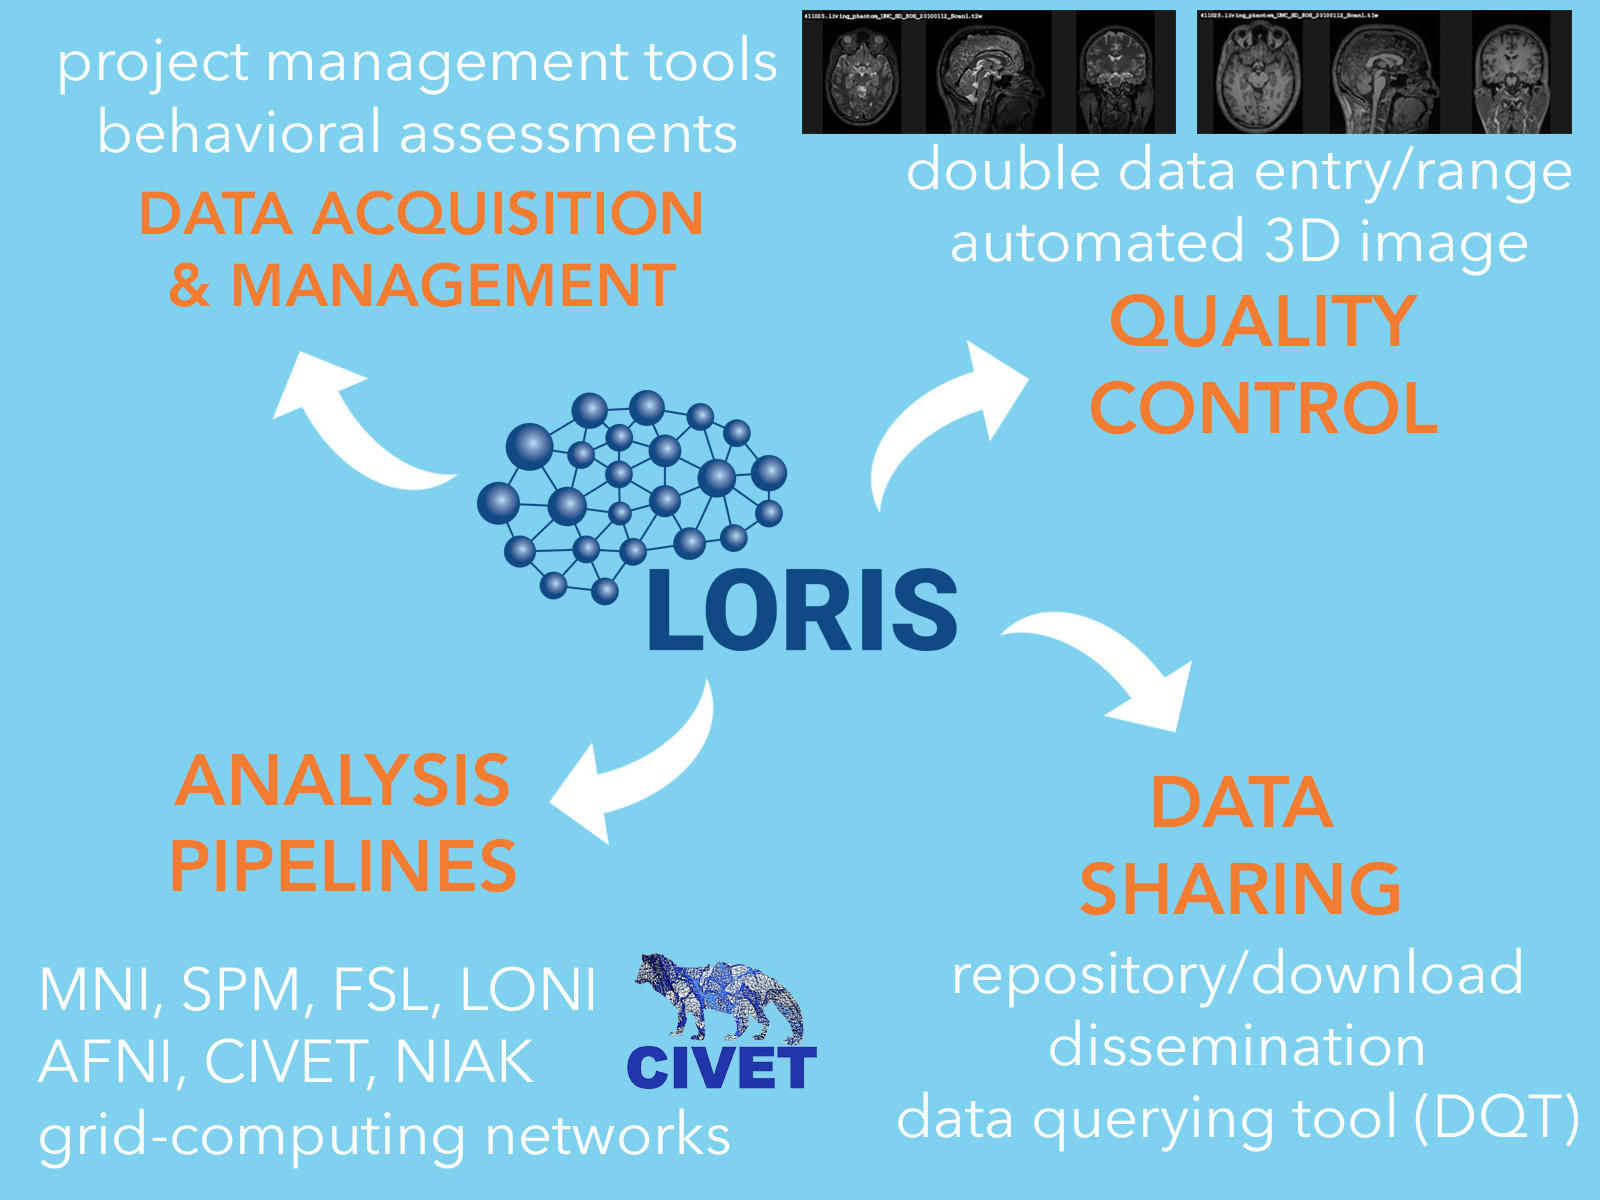

What does LORIS do?

What does LORIS do?

What does LORIS actually do?

1. Acquisition & Storage

2. Visualisation:

Imaging Browser, BrainBrowser3. Quality Control:

Radiological Review Module, DCC MRIData Querying

- Imaging Statistiscs

- Data Querying Tool (DQT)

- Quality Control - Protocol violations, artefact detector, inter-rater reliability

- Processing Platform - Seamless serving of data to processing environments